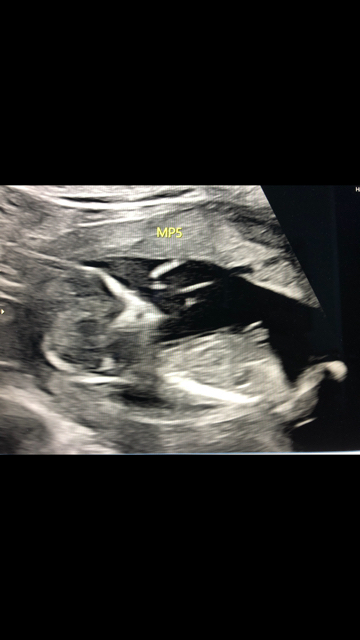

Any thoughts - boy or girl?

I’ve been waiting almost three weeks for my Natera results! Really want to know the sex of my baby. Any ideas based on my most recent ultrasound? These were taken at 12 weeks.